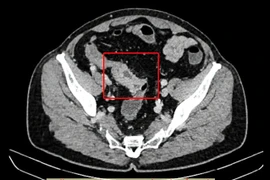

Cứu sống Việt kiều Mỹ bị bán tắc ruột do khối u đại tràng

Khi có các dấu hiệu bất thường về đường ruột như thay đổi thói quen đi tiêu, đau bụng kéo dài, phân có máu hoặc nhầy, người bệnh nên chủ động thăm khám sớm.